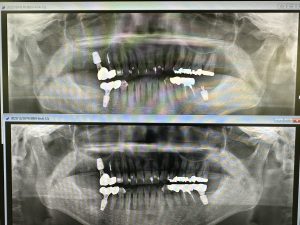

次はI.O.S印象、ソケットリフト2か月で印象

I.O.S74